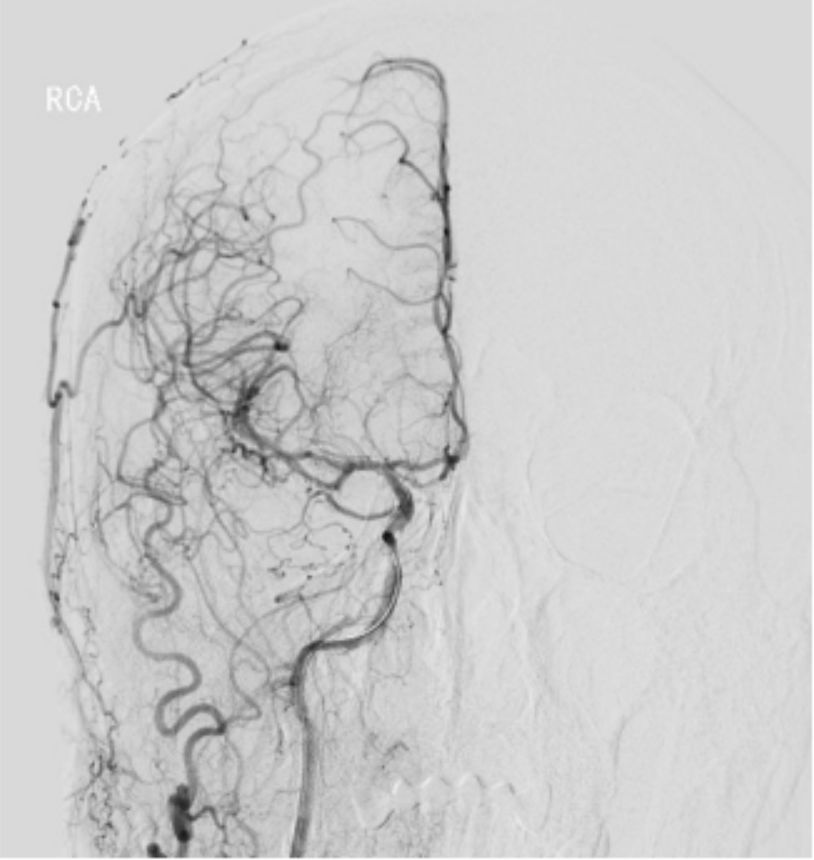

撤出PILOT 50微导丝,沿MOMA送入Synchro微导丝(0.014"x190 cm)+Headway 21微导管至右侧颈内动脉C1段,撤出微导管,将Synchro微导丝送入右侧大脑中动脉M1段,沿Synchro微导丝送入WALLSTENT支架(9 mmx50 mm)至C1段末端,定位准确后充盈MOMA球囊释放支架成功,抽瘪MOMA球囊,撤出支架输送装置。造影显示支架完全覆盖C1狭窄段(图9)。

图9

与血管壁贴合良好,无急性血栓形成。远端未放支架血管残余狭窄仍较重,沿Synchro微导丝送入Ultra-soft球囊(2.5 mmX20 mm)球囊,使用MOMA近端保护技术,依次由远到近对残余狭窄段进行扩张(图10),造影显示残余狭窄段较前改善。观察10 min,行右侧颈总动脉正侧位造影,显示右侧大脑中、前动脉及分支动脉显影良好,可见支架内血流通畅,无急性血栓形成(图11)。

图10

图11

撤出Synchro微导丝及MOMA,手术结束。术后患者诉左侧肢体无力症状明显改善。

讨论思考

此患者特点是右侧颈内动脉C1-C4段闭塞,右侧颈外动脉侧枝向右侧眼动脉代偿供血,并返流至右侧颈内动脉颅内段,向右侧大脑中、前动脉供血。手术过程中微导丝通过闭塞段,微导管通过闭塞段困难,撤微导管的过程中使用了球囊锚定技术固定微导丝。球扩时首先选择小球囊扩张狭窄段,然后根据造影情况逐步选用直径较大的球囊预扩,循序渐进开通血管,最后C1段置放WALLSTENT支架,残余段狭窄再次使用球囊扩张,观察10 min,行右侧颈总动脉正侧位造影,显示右侧大脑中、前动脉及分支动脉显影良好,开通手术成功。手术过程曲折,但结局良好。术后患者诉左侧肢体无力症状明显改善,远期疗效尚待观察随访。